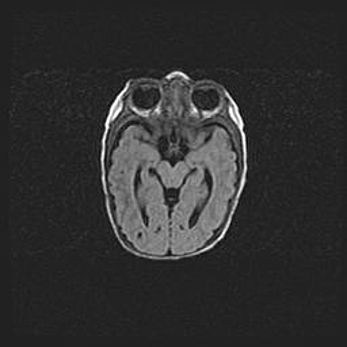

Лейкомаляция с кистозно-глиозной дегенерацией головного мозга.

Возраст: 2 месяца 25 дней

Вес: 6400 г

Окружность головы: 40 см

Срок гестации: 41 неделя

Лейкомаляцию относят к ишемически-гипоксическим повреждениям головного мозга, диагностируемым у новорожденных. При лейкомаляции в головном мозге обнаруживают очаги некроза, возникшие после тяжелой гипоксии и нарушения кровотока. В процессе морфогенеза очаги проходят три стадии: 1) развития некроза, 2) резорбции и 3) формирования глиозного рубца или кисты. Перивентрикулярная лейкомаляция (ПЛ) встречается примерно в 12% случаев среди новорожденных, обычно – у недоношенных детей, причем, частота ее зависит от массы, с которой младенец появился на свет. Наибольшее число малышей страдает лейкомаляцией, если масса при рождении 1500-2500 г.